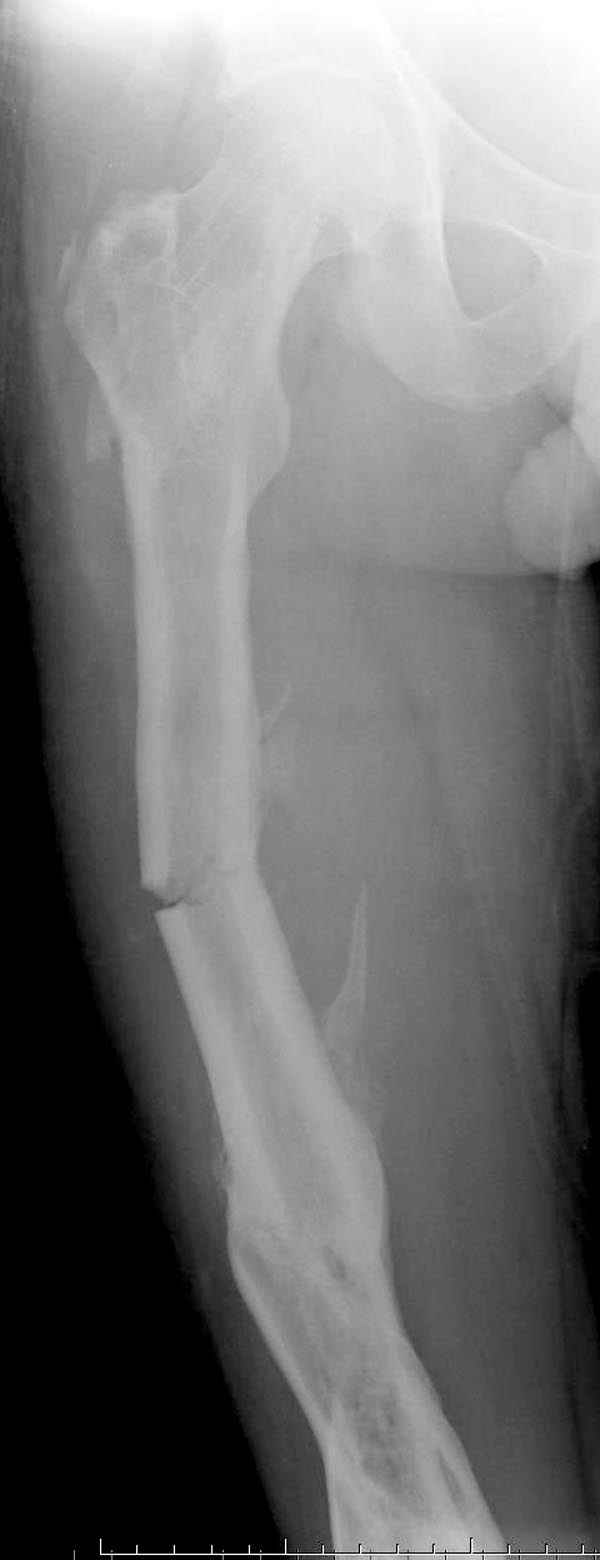

Представляю снимки больного с политравмой: леченного в другом мед.учреждении по поводу открытого перелома бедра, сперва аппаратом наружной фиксации, затем пластиной. Обратился к нам через 8 месяцев после удаления пластины с проблемой несросщего перелома бедренной кости, без клинических проявлении к инфицированию (не все снимки сохранены)

Рутинный интрамедуллярный остеосинтез с расверливанием и с фиксацией реконструктивным трокантерик штифтом (рис №1, №2),

если первые 4 месяца послеоперационного периода проходил без проблем, но на 5 месяце появились боли в дистальном отделе бедра и температура, т.е. симптомы медуллярного инфицирования (рис №3, №4).

Замена реконструктивного штифта “Custom made Nail” с антибиотиком (рис №5, №6),

после промывки канала с рассверливанием внутреннего кортекса, через 4 недели антибиотический штифт удалили, оспалителный процесс остановлен и бедро сросся.

Мы не дождались “Happy End”, у больного IQ в пределах 70%, через 6 месяцев вернулся после небольшой травмы, споткнувшись получил перелом

того же бедра (рис №7).

На следующий день произвели интрамедуллярный остеосинтез: этапы во время операции (рис №8, №9)

и последующих снимках (рис №10, 11, 12, 13) перелом сростается и передвигается с полной нагрузкой.

При обзоре причин перелома, на снимке №2 обнаружили, что один из стержней аппарата наружной фиксации проходил только через передний кортекальный слой, что создало стрессовую зону на бедре и в результате перелом из-за незначительной травмы.